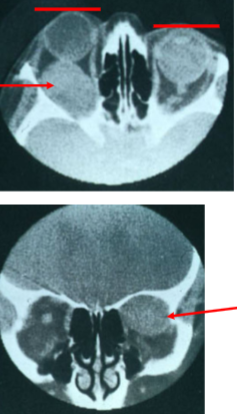

what are the radiologic features of a pituitary adenoma?

hyperostosis

no snowman on MRI

describe the appearance of a meningioma on imaging